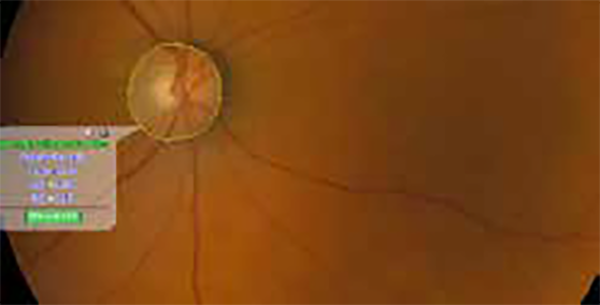

Gli strumenti di misura integrati nel software VX consentono di calcolare facilmente il rapporto C/D (cup-to-disc) per il rilevamento delle patologie legate al Glaucoma.

Protocollo Glaucoma

The SOLIX glaucoma package delivers in-depth analysis of the optic nerve head structure and vasculature. Optovue-exclusive scans bring additional insights that aid in clinical decision making.